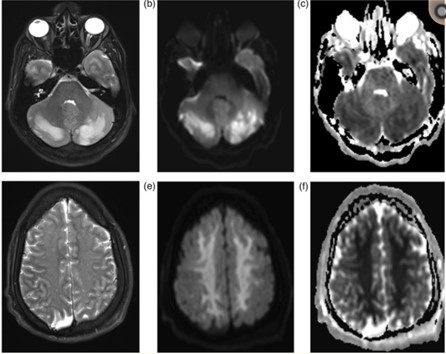

En la literatura se encontró caso de una mujer de 42 años, consumidora esporádica de MDMA, quien acudió a la guardia con síntomas de cefalea, alteración visual e hipertensión por síndrome de encefalopatía posterior reversible. Las imágenes radiológicas permitieron observar edema córtico-subcortical bilateral confluente de predominio parieto-occipital posterior. A partir de las imágenes radiológicas se pudo intervenir a través de un tratamiento con soporte y control de la presión arterial. (18) (ver Imagen 10).

Asimismo, una investigación encontró patrones comunes de lesiones cerebrales a través de la neuroimagen mediante una recopilación extensa de estudios radiológicos vinculados con casos de adolescentes con problemas de adicción a sustancias psicoactivas ilegales, desde 2006 hasta 2016. El estudio constató dos patrones coincidentes. El primero fue la lesión cerebral difusa simétrica de la sustancia blanca subcortical con afectación cerebelosa preferencial, o leucoencefalopatía. El segundo lo constituyen múltiples focos de infartos isquémicos en una distribución territorial no arterial patrón isquémico.(21)

En esta investigación que se viene señalando, se puede mencionar el caso de un joven de 16 años, con alteración aguda del estado mental por inhalación de vapor de heroína. Se le efectuó una RM que evidenció hiperintensidades en T2 de la sustancia blanca simétrica difusa infratentorial y supratentorial. El diagnóstico clínico en este caso fue rabdomiólisis, que afecta predominantemente la musculatura posterior del cuello(21) (ver Imágenes 11 y 12).

Otro caso que merece ser comentado es el de un adolescente de 15 años que presentó encefalopatía y signos extrapiramidales por ingestión de metadona. La RM evidenció focos de infartos agudos en el caudado y putamen, así como infartos corticales de la línea divisoria de aguas parietales(21) (ver Imagen 13).